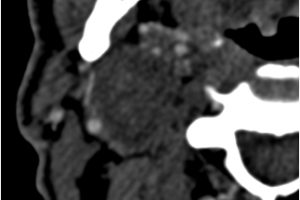

В мае 2019 года хирургами центра сосудистой хирургии им. Т. Топпера была выполнена уникальная операция по удалению гигантского образования шеи, которое давило на сосуды и нервы, угрожая жизни пациента. При исследовании структуры опухоли под микроскопом было установлено, что это шваннома (невринома) – вид доброкачественной опухоли, произрастающей из клеток миелиновой оболочки нерва. Послеоперационный период протекал гладко и на 7 сутки в удовлетворительном состоянии пациент был выписан.